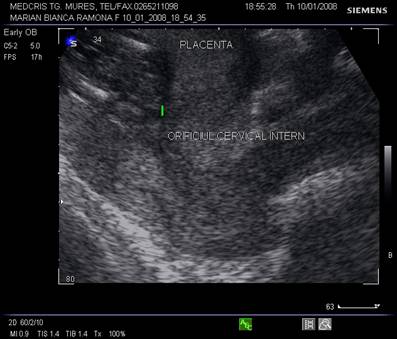

Diagnosticul ecografic se face urmarind marginea placentara inferioara si raportul cu orificiul cervical intern. O imagine mai buna necesita vezica urinara in semipletie sau chiar o ecografie transvaginala.

Fig. nr.217. Placenta praevia centrala la 15 saptamani ( linia indica raportul placenta praevia cu orificiul cervical intern)

Fig. nr.218. Placenta praevia complet centrala , la aceeasi sarcina ca in figura precedenta, dar la 28 saptamani gestationale

Fig. nr.219. Placenta praevia marginala , la nivelul orificiului cervical intern marcat cu linie, se observa marginea inferioara a placentei, inserata pe peretele uterin anterior